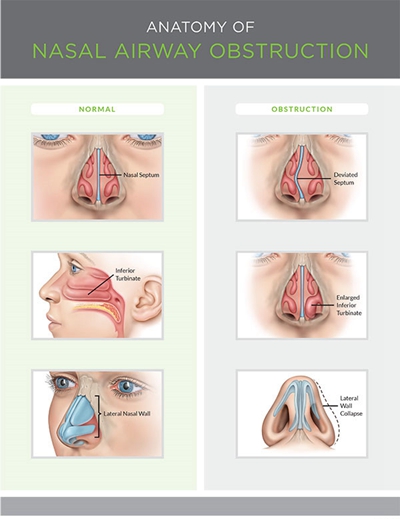

鼻中隔偏曲圖片

A:鼻中隔偏曲會引起病人出現臨床症狀,造成各種危害,常見危害如下:1、鼻塞:鼻中隔偏曲如果是向一側鼻腔偏曲,開始的時候會引起一側鼻塞。隨著對側下鼻甲的代償性肥厚會引起雙側鼻塞,這時不能經過鼻呼吸,通常用口腔呼吸,會造成打鼾,尤其有些病人會出現……

A:鼻中隔是分隔兩側鼻腔位於中間的結構,表面覆蓋有黏膜,黏膜下有鼻中隔的骨質和軟骨,鼻中隔偏曲大多數是先天性的。有部分患者是後來鼻子受過外傷、撞擊,造成的鼻中隔偏曲,大多數人的鼻中隔偏曲症狀不嚴重,叫生理性的彎曲,並不需要治療、不需要手術。只……